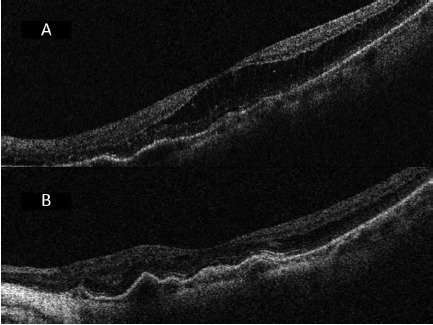

5.png

图 5 A 为后巩膜葡萄肿黄斑劈裂合并脱离且无黄斑裂孔患者术前 OCT;B 为同一只眼术后 12 周 OCT ,黄斑劈裂以及脱离完全恢复,黄斑、脉络膜以及巩膜扣带处变平(扣带组)

6.png

图 6 A 为后巩膜葡萄肿黄斑脱离合并裂孔患者眼术前 OCT,视网膜前膜表现为切向牵引力;B 为同一只眼术后 8 周 OCT 显示黄斑劈裂以及脱离几乎完全恢复,黄斑、脉络膜以及巩膜扣带处变平,视网膜前膜仍表现为切向牵引力(扣带组)